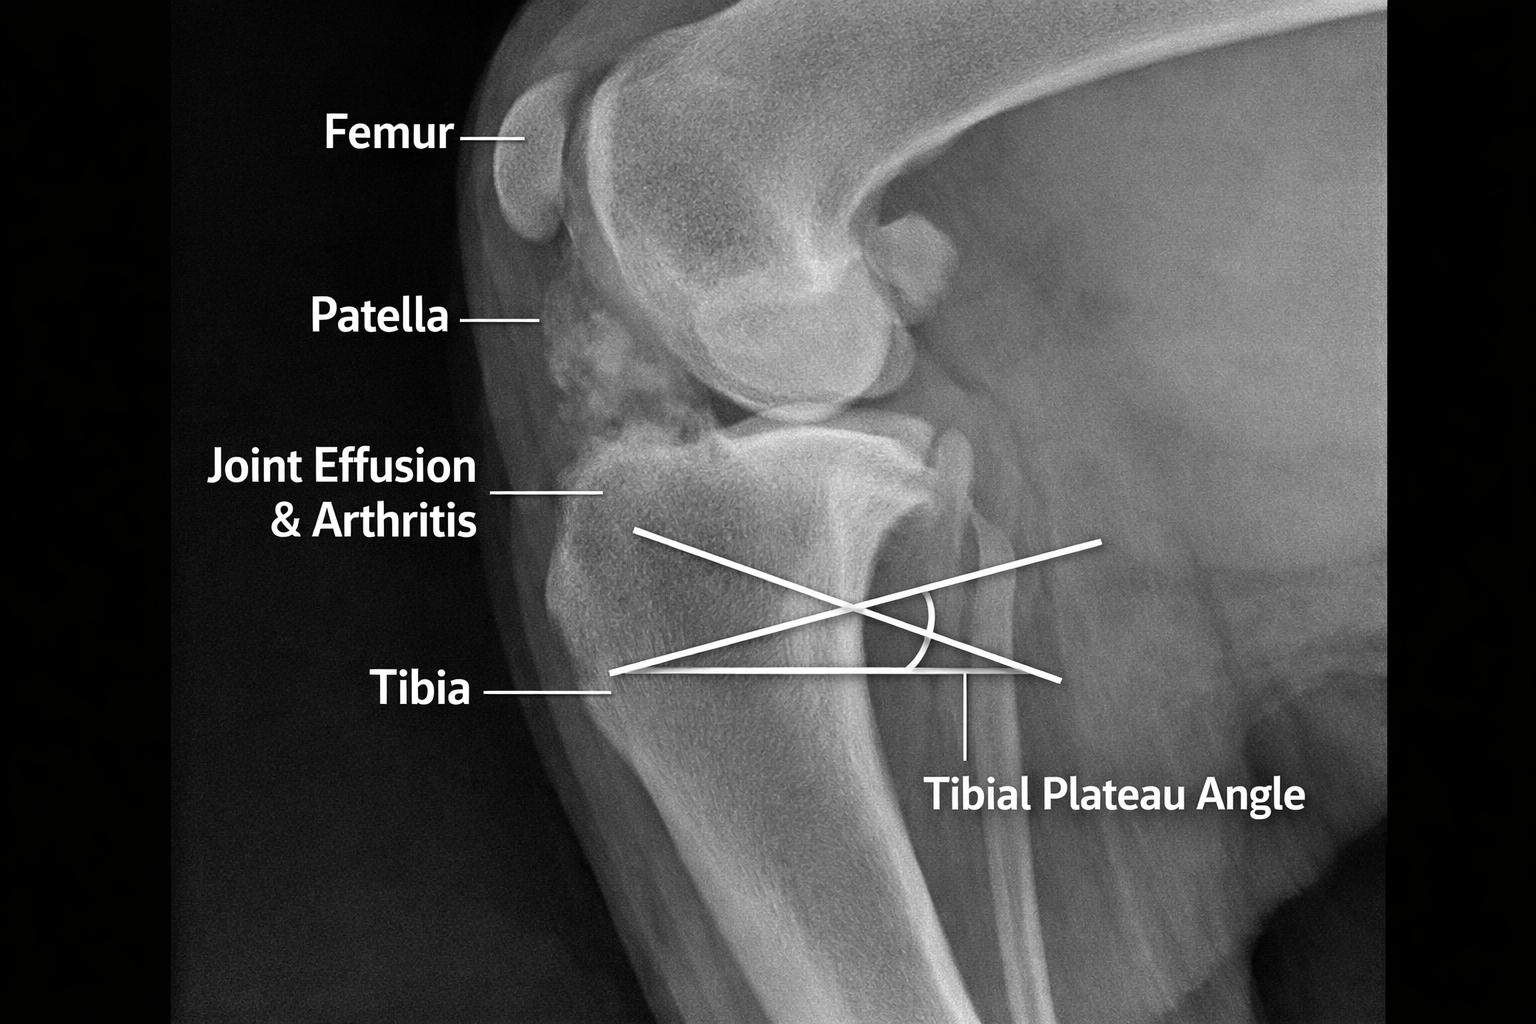

Tibial Plateau Angle (TPA)

The TPA is measured on radiographs and determines the degree of rotation needed during surgery:

- Normal TPA: 22-25 degrees

- Post-TPLO goal: 5-6.5 degrees

- This measurement is critical for surgical planning

- Measure the tibial plateau angle